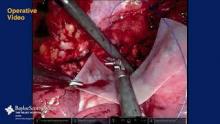

This video demonstrates robotic-assisted repair of a Morgagni diaphragmatic hernia using mesh through a thoracic approach. The patient was a 52-year-old woman who was found to have a Morgagni diaphragmatic hernia with incarcerated omentum during a sleeve gastrectomy 4 years earlier. Repair was not done transabdominally due to the proximity to the heart. During the intervening 4 years she had a 100 lb weight loss, but intermittent severe right anterior chest pain at the costal margin. CT scan demonstrated a 2 to 3 cm right anterior diaphragmatic hernia with incarcerated omentum consistent with a Morgagni diaphragmatic hernia. She underwent robotic-assisted repair with acellular mesh. The patient was discharged home on the 1st postoperative day. Follow-up demonstrated resolution of her chest pain.

The thoracic approach allows dissection and reduction of the hernia with safe mesh repair close to the heart. Robotic assistance offers improved vision and a more stable platform resulting in reduced pain, shortened length of hospital stay, and enhanced recovery.